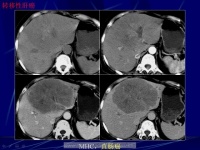

2.B型超生显像可显示直径2cm以上的肿瘤,对早期定位检查有较大的价值;电子计算机X线体层摄影(CT) 可显示直径1.0cm以上的肿瘤;放射性核素扫描 能显示直径3-5cm以上的肿瘤;其它X线肝血管造影、核磁共振像对肝癌诊断有一定价值。

影像学检查